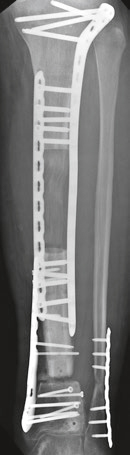

Вот эти картинки особенно зацепили.

Имя     : 31.jpg

Url     : http://weborto.net:8080/pipermail/ortho/attachments/20180207/e1f20354/attachment-0002.jpg